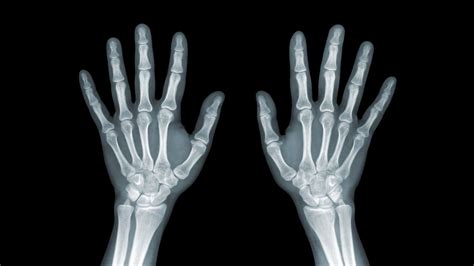

Artritis Periférica Mano, or peripheral arthritis of the hand, is a condition that affects the joints of the hand and wrist, causing pain, stiffness, and swelling. This condition can significantly impact daily activities, making even simple tasks challenging. Understanding the causes, symptoms, and treatment options for Artritis Periférica Mano is crucial for managing this condition effectively.

• Imaging Tests: X-rays, MRI, or ultrasound to visualize the joints and identify any structural abnormalities.